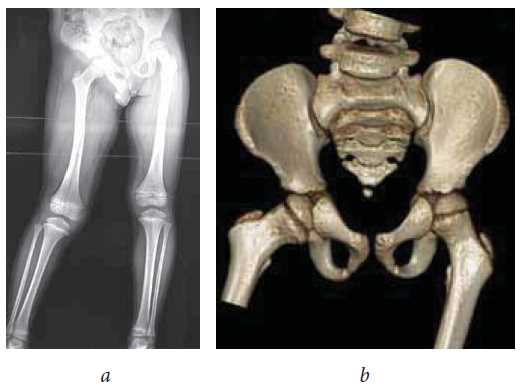

X-ray examination was performed using Digital Diagnost v.2 apparatus and spiral computed tomography (CT) was performed using Philips Brilliance cT apparatus. These examinations indicated changes in the form of pelvic skew, abduction of the right lower limb, and diaphysis deformity of the right femur which indirectly indicated the presence of fibrous cords in the soft tissues of the right thigh (Fig. 2).

Fig. 2. X-ray of the lower limbs in the standing position (a), and CT of hip joints (b) of patient D, aged 6 years, before surgery